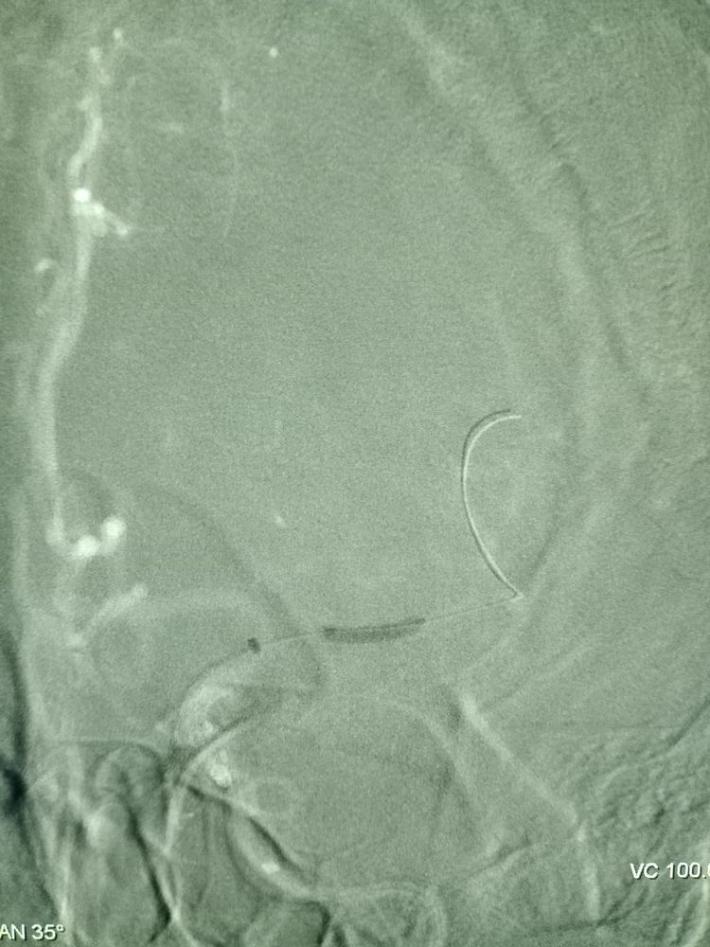

国产取栓支架尼科4mm*20mm成功打开,前向血流恢复。

球囊扩张